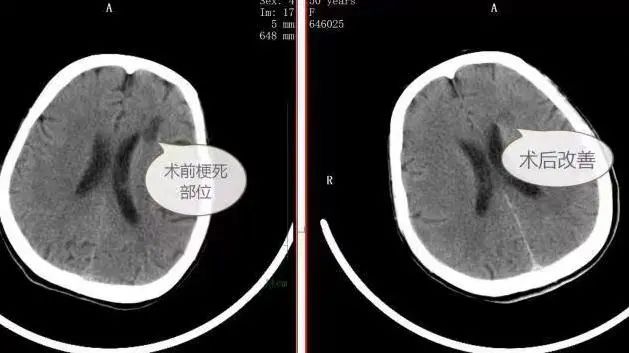

术后复查TCD可见脑血流恢复良好,头部CT提示左侧大脑低密度灶(梗死)部位改善,患者术后语言功能有所恢复,右侧肢体肌力有所恢复,能自己独立行走,住院观察1周左右顺利回归正常生活。